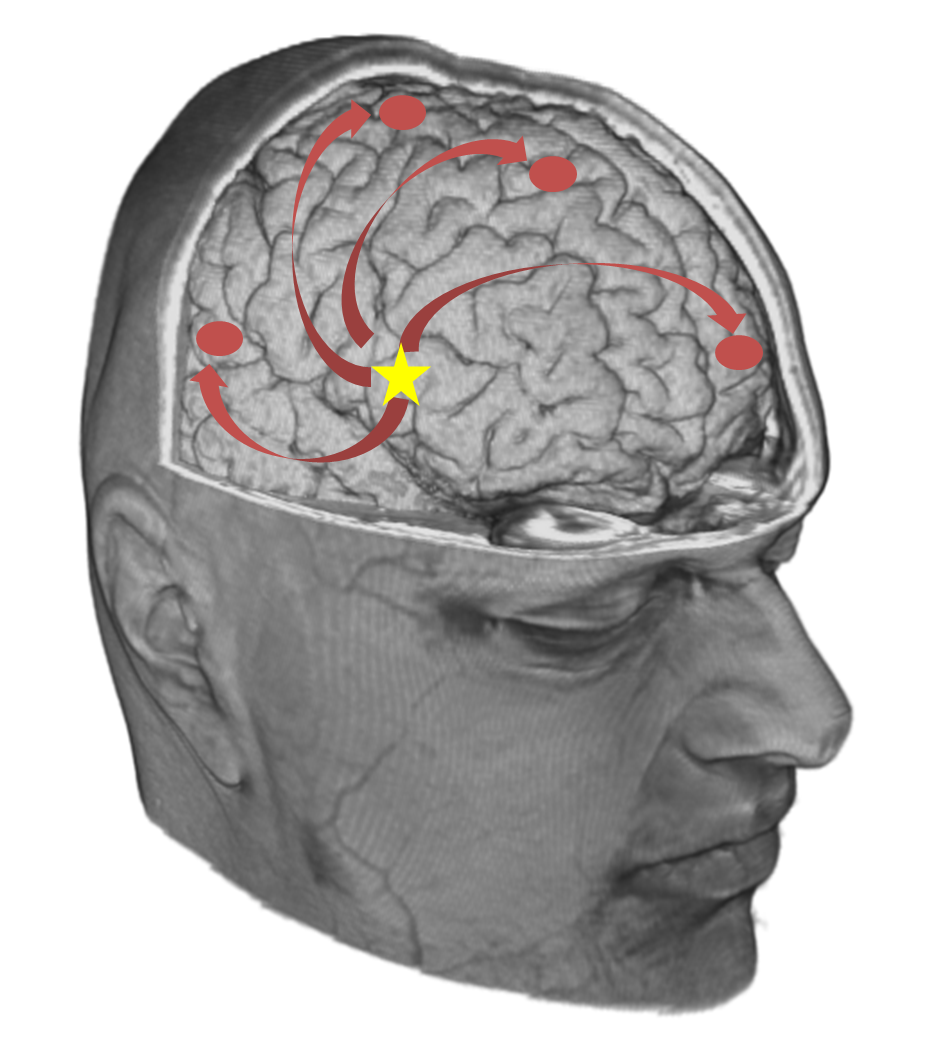

In the first stage a non-invasive tool, ElectroEncephaloGraphy (EEG), will be used to measure the electric field of the brain through electrodes placed on top of the scalp. By measuring the voltage difference between the EEG electrodes the electric field of the brain can be studied with a high temporal resolution (ms). Recently, high density EEG (hd-EEG) systems have been developed with up to 256 electrodes. These systems allow more accurate measurements compared to the old systems having only ± 32 electrodes. The FBM Lab is one of the few labs that have hd-EEG recordings of epilepsy patients. In this project we will develop an algorithm to investigate the brain networks in epilepsy patients based on hd-EEG recordings. The brain networks will be studied to localize the epileptic focus, the brain region that causes the seizures.

In the second stage hd-EEG will be combined with functional Magnetic Resonance Imaging (fMRI) that images the concentration of oxygen in the brain with a high spatial resolution (mm). The simultaneously recorded hd-EEG / fMRI allows studying the brain networks with both a high temporal and spatial resolution. Furthermore, fMRI is more sensitive to record brain activity of deep brain structures compared to hd-EEG. The added value of combining hd-EEG with fMRI to localize the epileptic focus will be assessed.